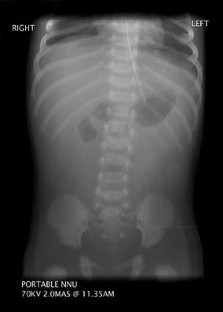

Fig. 1